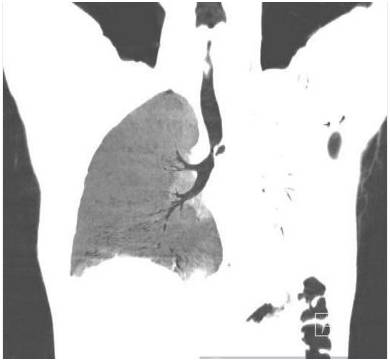

胸部前后位示弥漫不均匀的异常密度影,左肺体积缩小,左肺门区肿块样影与心膈角呈钝角。未增强纵隔窗CT示左肺肺不张,左主支气管完全受阻。增强CT示左主支气管及其段支气管内非强化的肿块。最小密度投影示左肺叶远端支气管重度狭窄,左主支气管及以下层面受阻。